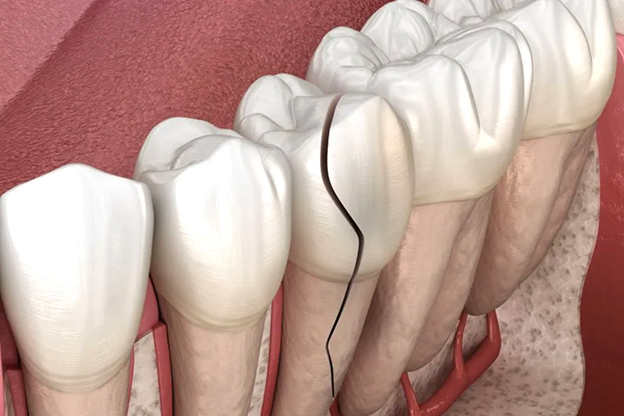

- ⚡ Tủy viêm do lỗ sâu lớn hoặc răng nứt

- Khi vi khuẩn xâm nhập sâu vào tủy qua lỗ sâu hoặc vết nứt, tủy bị kích thích mạnh, áp lực trong tủy tăng, gây đau nhức dữ dội, đau nhói. Cơn đau thường tăng lên khi ăn, nhai, hoặc tiếp xúc thức ăn nóng/lạnh, và không giảm khi dùng thuốc giảm đau thông thường. Đây là lúc bạn cần điều trị tủy chuyên sâu tại nha khoa để loại bỏ vi khuẩn, giảm đau và bảo tồn răng.

- ✨ Chấn thương răng hoặc răng bị vỡ

- Răng bị gãy, nứt hoặc chịu tác động ngoại lực sẽ làm tủy răng lộ ra ngoài. Đây là điều kiện lý tưởng để vi khuẩn tấn công trực tiếp, gây viêm tủy cấp tính nếu không được điều trị kịp thời, đồng thời làm tăng nguy cơ mất răng vĩnh viễn.